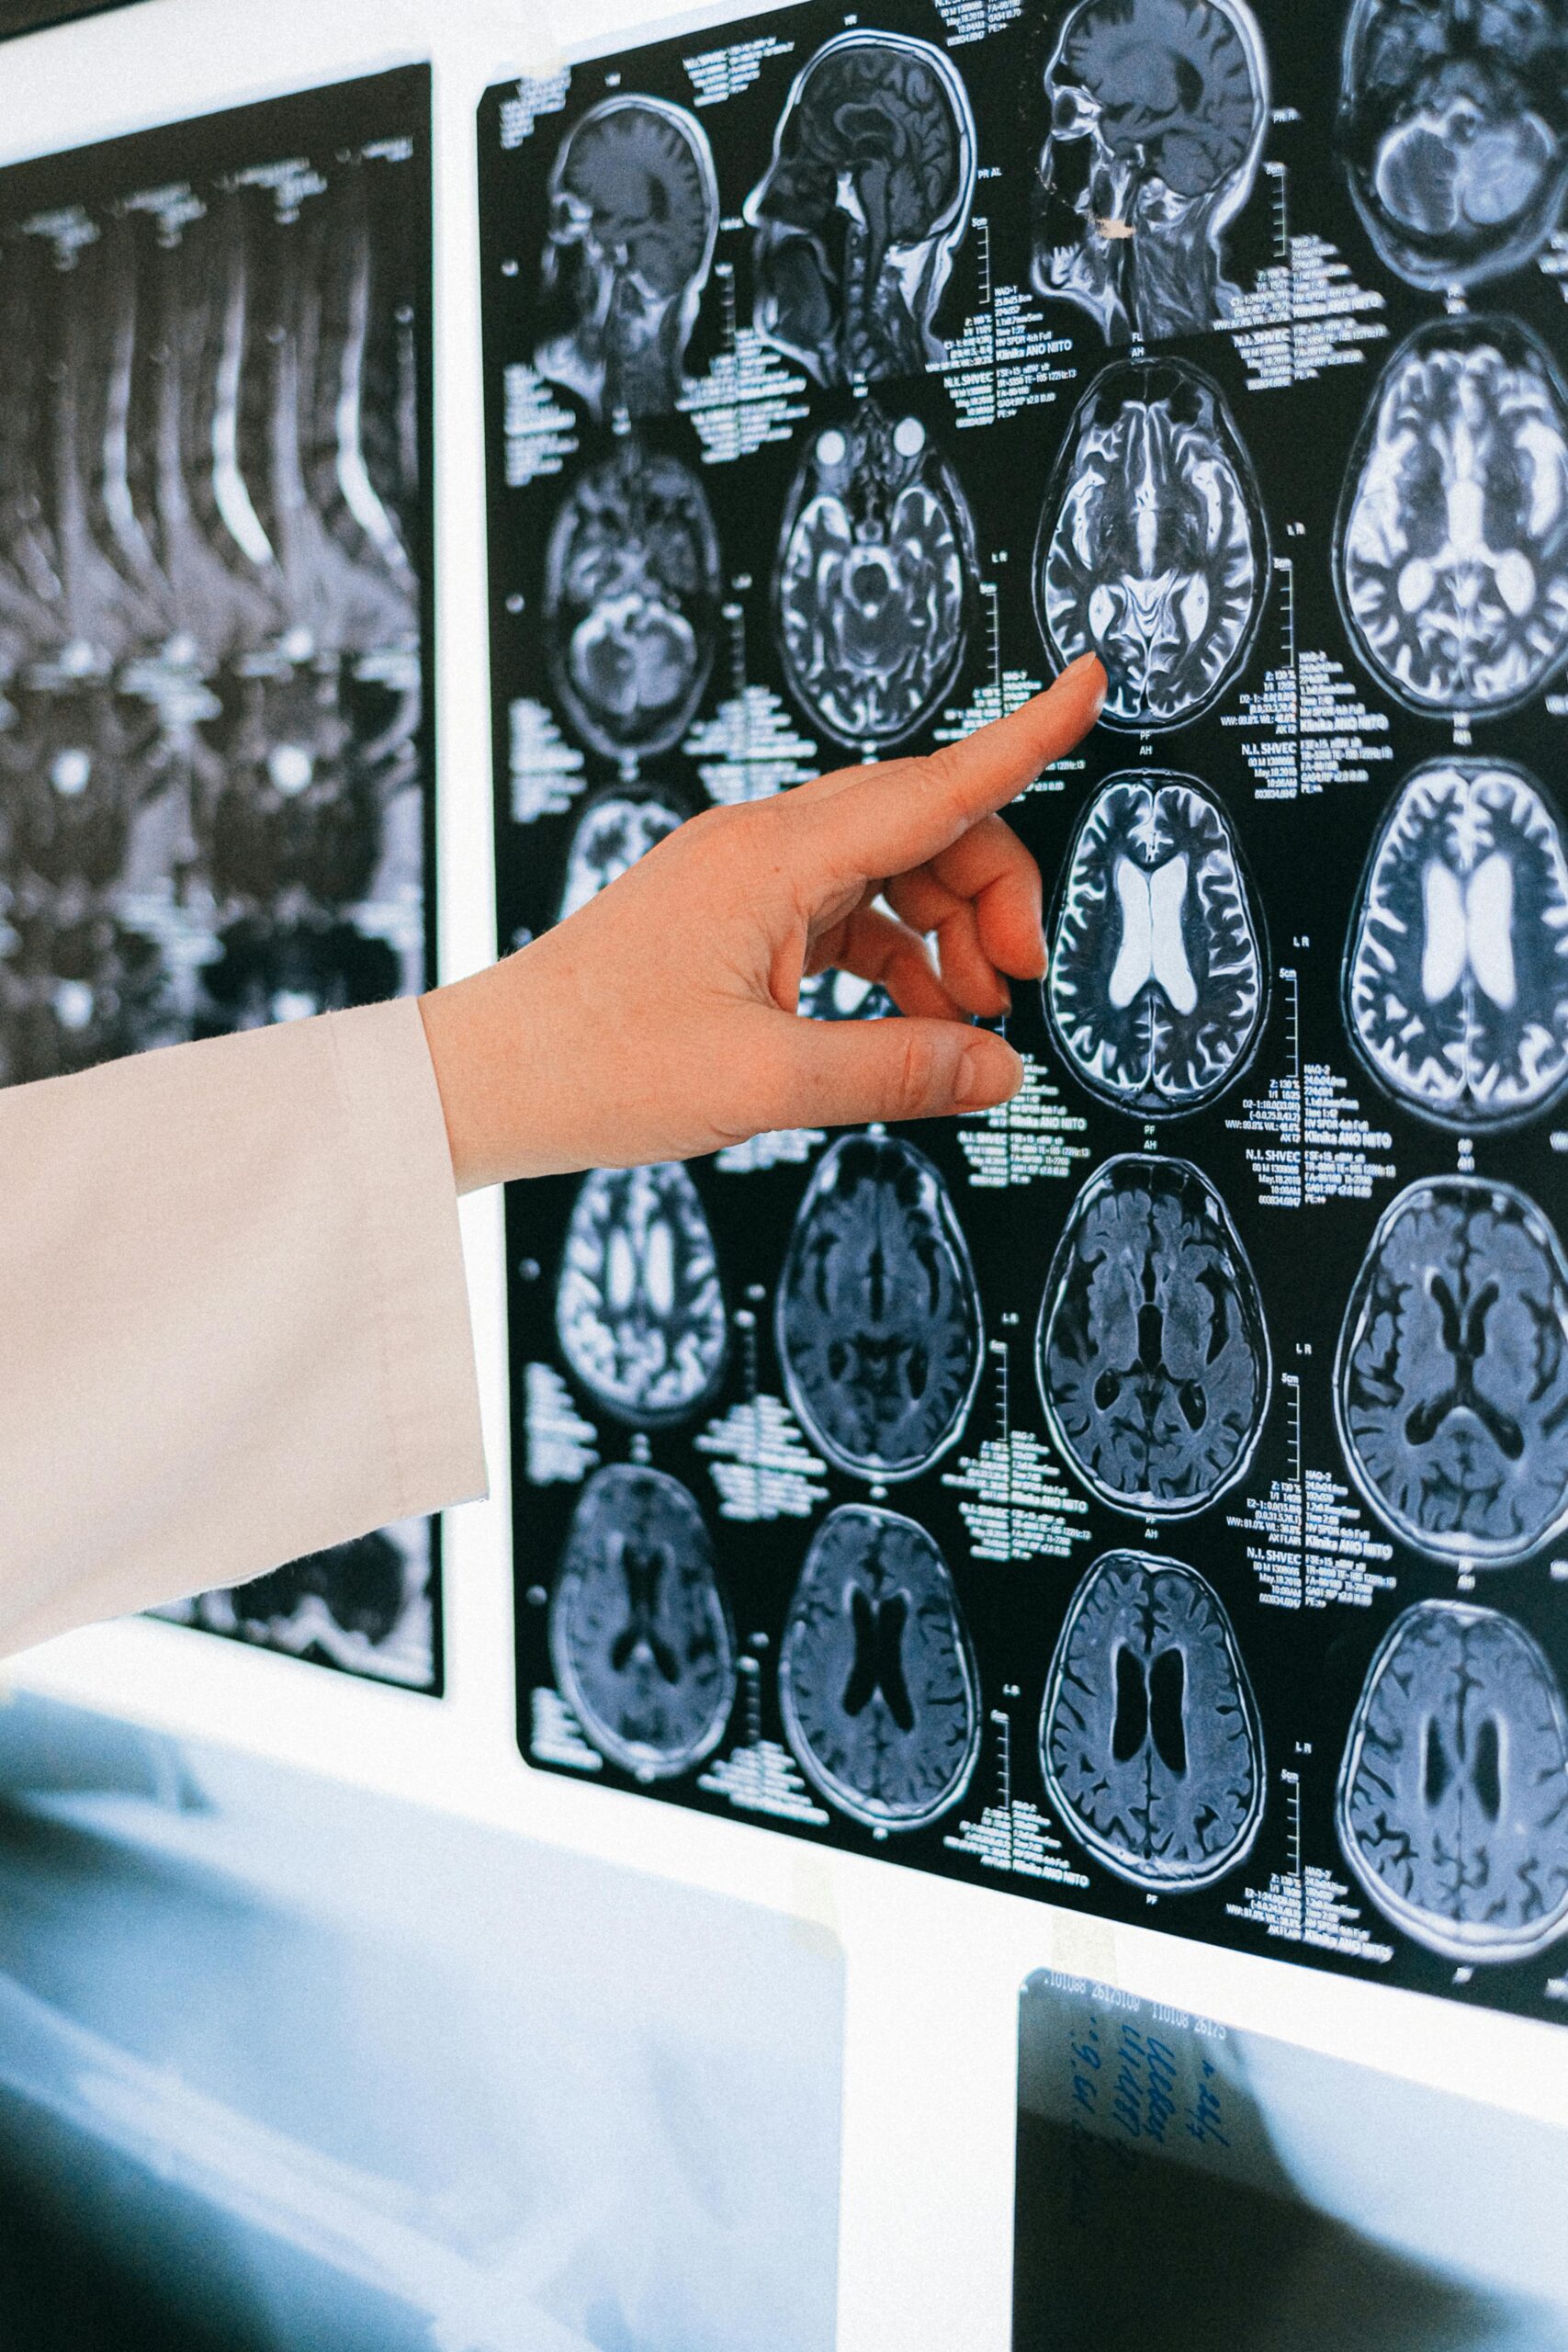

Radiology